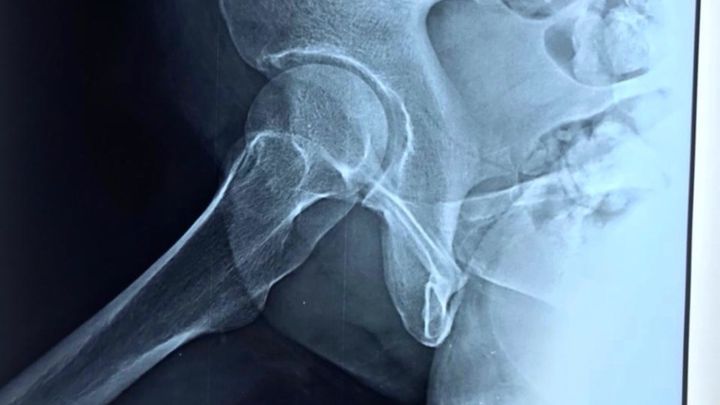

In February this year (2021), my mother was hit by a delivery van and they accidentally seriously fractured her hip bone. She couldn’t move for a month while she got rest & treatment. She had pre-existing issues with her uterus since December 2020.